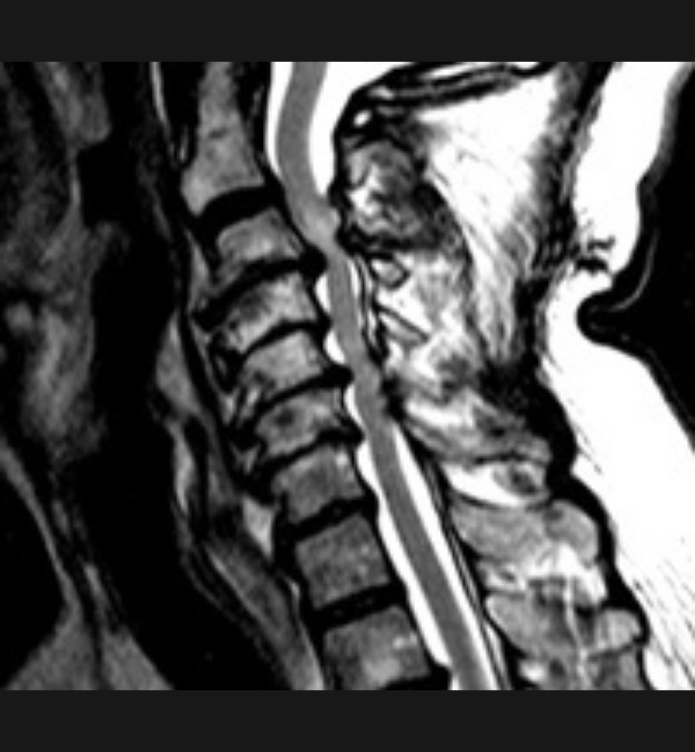

Basit Omurga ve Omurilik Anatomisi Omurga, 33 adet omur kemiğinden oluşur. Bu kemiklerin 7 tanesi boyun omuru, 12 tanesi sırt omuru, 5 tanesi bel omurudur. Beş tanesi birleşmiş olarak sakrum denilen kemiği ve 4 tanesi yine birleşmiş olarak koksiks denilen kuyruk sokumu kemiğini oluşturur. Omurganın görevi omuriliği korumak ve gövdeyi dik pozisyonda tutmak için destek […]